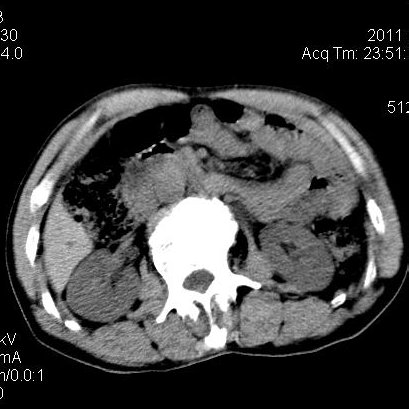

肝左叶发育异常

男性,55岁,骑摩托车摔倒后入院,自述右上腹疼痛

[backcolor=#FF0000]第一次诊断的时候也是这么肯定,可是床旁超声检查并没有发现明显异常,而且患者的一般症状都良好。还好临床只是保守治疗,没有立即手术,第二次复查的时候没有一点变化,又做了MRI检查,没有血肿,

这是一例肝左叶发育异常的,很个性吧~[/backcolor]